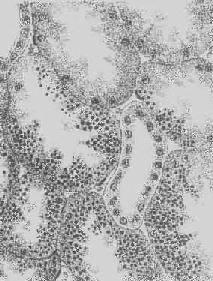

肝细胞脂肪变性

图1-18 肝细胞脂肪变性

肝细胞胞浆内出现大小不等的脂肪空泡;右上角为饿酸染色的脂肪细胞, 脂滴染成黑色